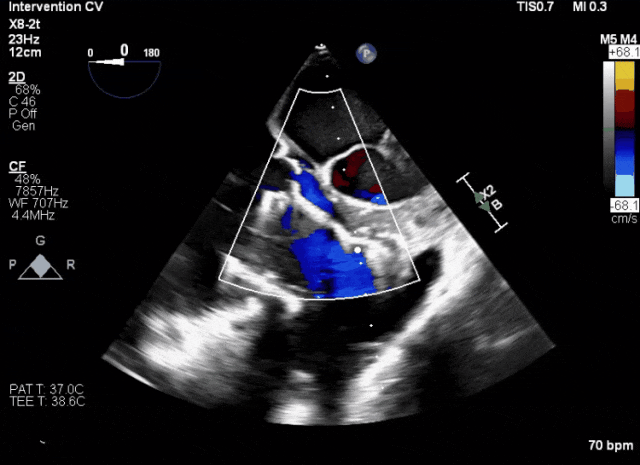

術后超聲顯示人工瓣膜穩(wěn)定性良好,瓣葉啟閉正常

術后DSA、超聲顯示人工瓣膜穩(wěn)定性良好,瓣葉啟閉正常,無瓣周漏

術后超聲評估瓣膜穩(wěn)定性良好,無瓣周漏